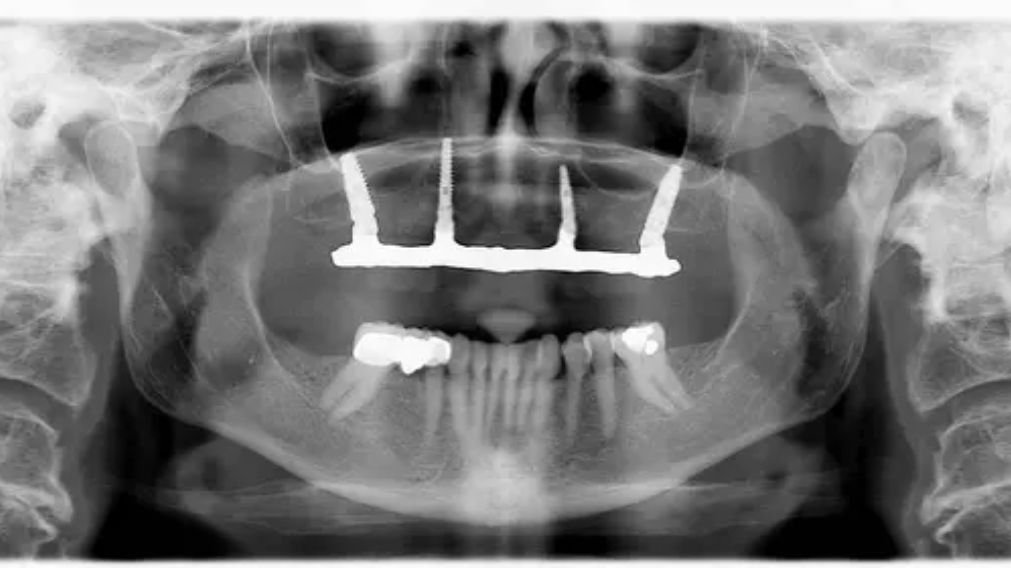

A única forma de saber com certeza se você pode fazer Implante Total em 1 Mês é através de uma avaliação completa com um especialista em implantes. Esta avaliação inclui:

- Exame clínico (avaliação da boca, dentes, gengiva)

- Radiografia panorâmica (visão geral dos ossos)

- Tomografia computadorizada (análise 3D da quantidade e qualidade óssea)

- Anamnese (histórico médico, medicamentos, hábitos)